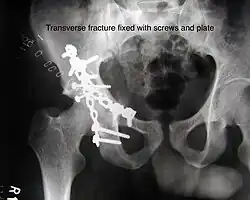

Transverse fracture fixed with screws and plate

The final management depends on the size of the fragment(s), stability and congruence of the joint. In some cases traction for six to eight weeks may be the only treatment required; however, surgical fixation using screw(s) and plate(s) may be required if the injury is more complex. The latter treatment will be called for if bone fragments do not fall into place, or if they are found in the joint, or if the joint itself is unstable.